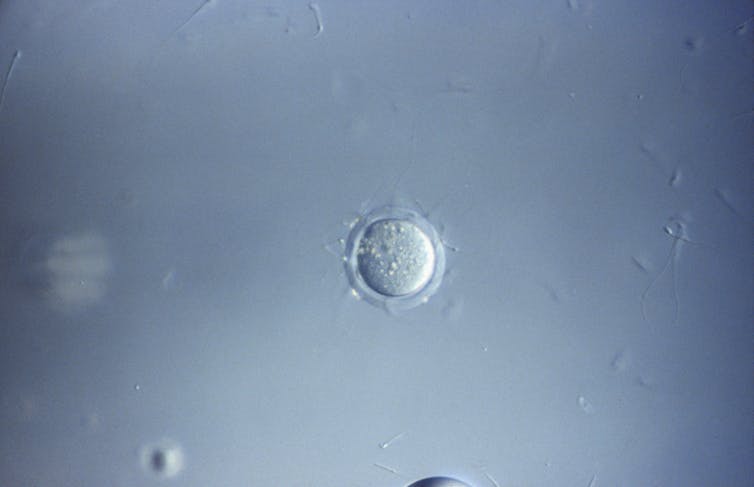

Assisted reproductive technologies are medical procedures that help people experiencing difficulty having or an inability to have biological children of their own. From in vitro fertilization to genetic screening to creation of viable eggs from the skin cells of two male mice, each new development speaks to the potential of reproductive technologies to expand access to the experience of pregnancy.

At a genome-editing conference in March 2023, researchers announced that they were able to delete and duplicate whole chromosomes from the skin cells of male mice to make eggs. This method is one potential way to make eggs that do not carry genetic abnormalities.

They were very upfront that this was done at 1% efficiency in mice, which could be lower in humans. That means something bad happened to 99% of the embryos. The biological world is not typically binary, so a portion of that surviving 1% could still be abnormal. Just because the mice survived doesn’t mean they’re OK. I would say at this point, it would be unethical to try this on people.